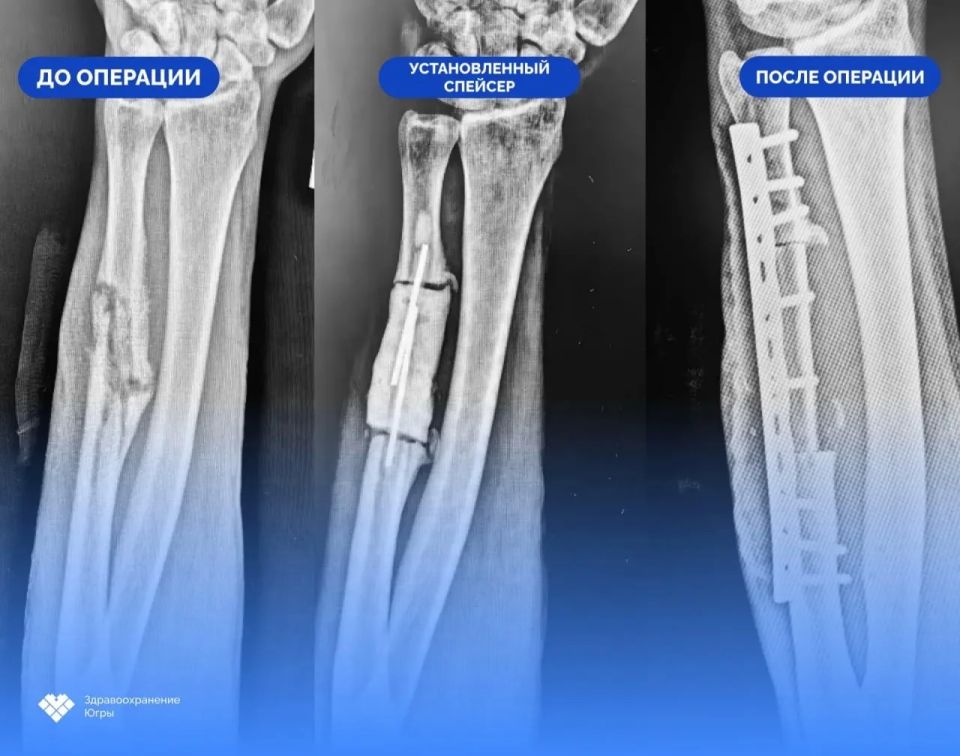

46летний югорчанин получил ранение при атаке дронов в начале августа. После долгого лечения в госпитале он обратился в Сургутскую травматологическую больницу с несросшимся переломом...